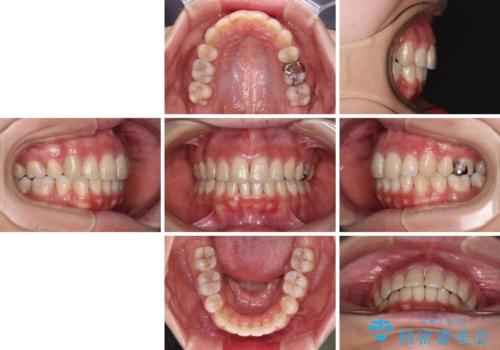

突出した口元が気になる ハーフリンガル装置による抜歯矯正

- 口元の突出感を気にして来院された患者様です。

通常では上下左右の第一小臼歯4本を抜歯しますが、下顎が左側にシフトしていたため、下顎左側のみ第二小臼歯を抜歯し、正中を合わせながら口元を下げる治療計画としました。